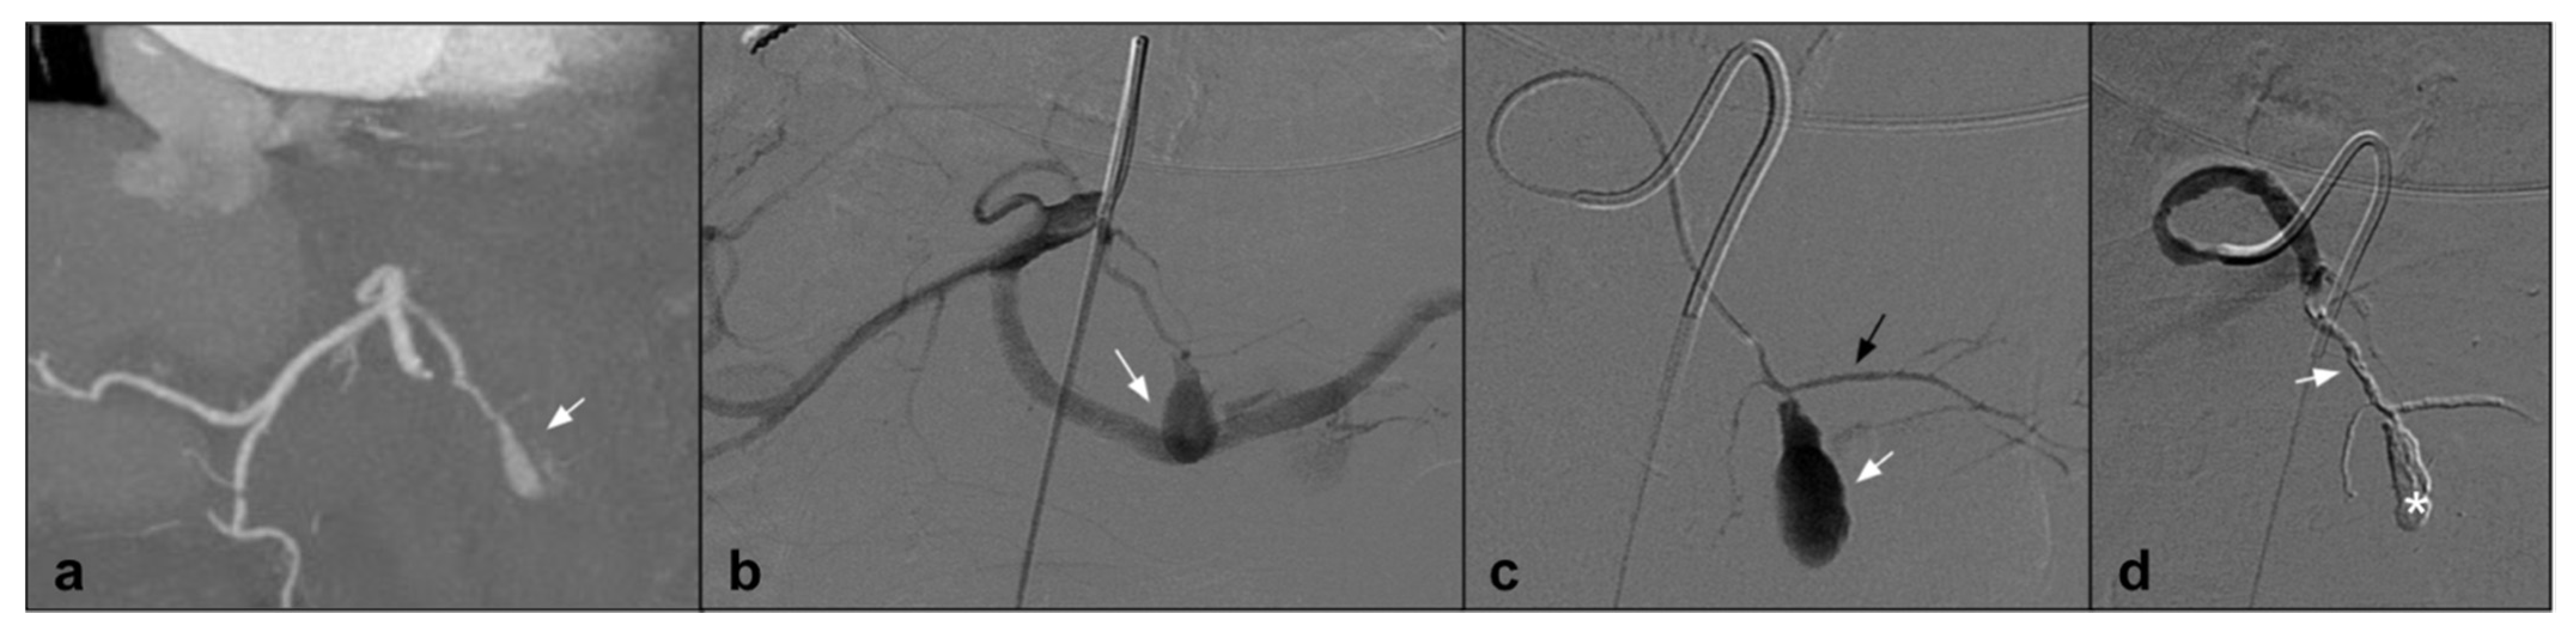

7. Endoleak

Endovascular abdominal and thoracic aortic aneurysm repair (EVAR and TEVAR) in patients with a suitable anatomy has become the preferred treatment for abdominal aortic aneurysm [44]. Those endovascular procedures provide a less invasive alternative to open repair with improved outcomes. The most common complication is represented by endoleaks, which may compromise long-term endograft viability, increasing the risk of rupture; therefore, long-term surveillance is needed and in specific cases secondary interventions are requested [45]. Endoleaks are classified on the basis of anatomical origin, among different types: Types I and II are the most common, and are usually treated through an endovascular procedure [46]. Nowadays, a surgical approach is performed only in cases of endovascular that are unsuccessful or a fast sac growth with a high risk of rupture. Among different approaches, endoleak treatment with coil embolization was widely used; however, it is associated with a high rate of endoleak recurrency. For the high reintervention rate, many investigators have refined their technique associating EVOH liquid agents with coils [47]. As shown by Ameli-Renani et al., since 2010, multiple scientific papers describing the use of liquid embolizing agents in treatment of Type I and II endoleaks have been published. In case of Type I (E1), endoleaks represent a vascular emergency due to the high risk of sac rupture. In those cases when the vascular anatomy does not allow an endograft extension or this technique is not successful, embolization with EVOH in association with coils or alone permits to obtain a complete seal of the aneurismatic sac [48]. Type II (E2) endoleaks are found the most following EVAR and also represent the main cause of reintervention [49]. As shown by Chung et al., E2 should be treated when persistent after 12 months from the EVAR procedure and associated with a significant sac size increase [50]. Earlier literature reports the use of coils alone to embolize E2; more recently, multiple articles have reported the use of liquid embolic agents alone or in association with coils. A recent study [47] showed that there is no clinical or statistical difference between the treatment of EL with coils or with Onyx alone, in a population of 17 patients treated with Onyx alone vs. 18 patients treated with coils and glue (There were no significant differences between the two groups regarding age, BMI, or sex). In looking at comorbid conditions, there was no difference in the incidence of hypertension, hyperlipidemia, coronary artery disease, prior myocardial infarction, congestive heart failure, atrial fibrillation, tobacco use, diabetes mellitus, or chronic kidney disease, showing no statistical differences in clinical, efficacy, and safety. In addition, Mozes et al. [44] highlights that EVOH, specifically Onyx, gives similar outcomes to other embolization strategies in the literature and He states that Onyx embolization for management of E2 needs to be judiciously considered, particularly for persisting E2. In addition, Venturini et al., in his review on the use of Squid Peri, described the efficacy and safety in being able to treat Type II endoleak with Squid in four cases, without evidence of complications and with 100% technical success [13] (Figure 3).

Figure 3.

(a) Axial CTA shows, the presence of Type II endoleak after EVAR, supplied by lumbar arteries (white arrow). (b) DSA performed with microcatheter positioned in a lumbar branch through the ilio-lumbar artery highlights the presence of hypertrophic lumbar circles (white arrow head) with sac refuelling (white arrow). (c) Post-procedure DSA shows the cast of Squid 12, which completely occupies the space of the endoleak in the sac (white arrow).

Theoretically, to obtain a successful E2 embolization, the endovascular treatment should be aimed close to the nidus cavity, which is easier to achieve with a liquid agent than multiple coils [49]. Furthermore, in specific cases when the vascular anatomy does not allow for reaching the proximity of the nidus, it is possible to inject low viscosity EVOH embolizing agents (Onyx 18, Squid 12) from a proximal location which could flow toward the culprit lesion [51]. As shown by Zener, Marcelin, and Carraffiello, E2 in cases of endovascular failure could be treated with a direct percutaneous sac puncture and embolization with liquid embolic agents [52,53,54]. Among the different NALEA for E2, Onyx is the most widely used followed by Squid. Recently, a case report describing a successful embolization of E2 using Phil has also been published [46,55] with similar results